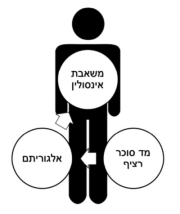

| 07:47, 15 בספטמבר 2023 | לבלב מלאכותי ביוני.png (קובץ) |  |

94 קילו־בייטים | Motyk | 1 | |

| 07:42, 15 בספטמבר 2023 | לבלב מלאכותי 1.png (קובץ) |  |

45 קילו־בייטים | Motyk | 1 | |